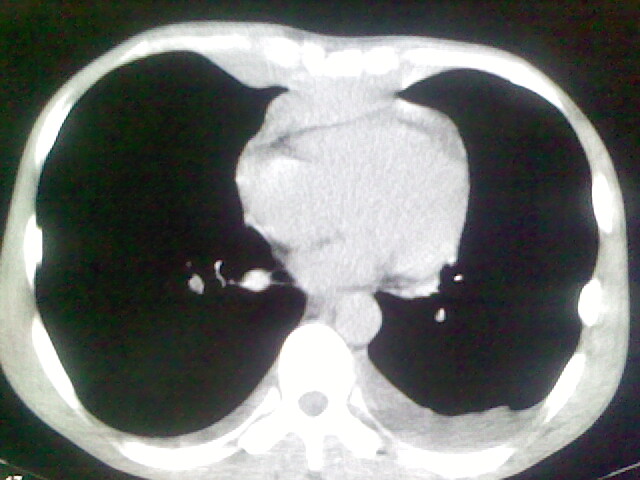

以下是引用杀毒软件在2008-9-3 6:11:00的发言:[br]侵袭性胸腺瘤------一般不侵到气管旁[br][br]考虑----纵隔淋巴瘤,心包及胸膜受累

以下是引用wzr在2008-9-3 5:30:00的发言:[br]侵袭性胸腺瘤

以下是引用随光逐影在2008-9-3 7:07:00的发言:[br]1)考虑淋巴瘤可能。2)双侧胸腔积液(以左侧为甚)。3)心包积液。